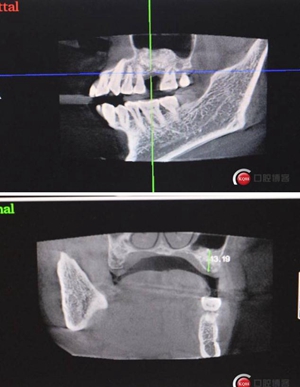

改良式外提升工具盒-外提 科貿(mào)嘉友收錄

大家好,我是梁老師的助理小依。由于梁老師每天手術(shù)檔期安排較滿,加上經(jīng)常出差講課,沒(méi)有時(shí)間整理病例 。為了方便大家更及時(shí)的了解梁老師最新手術(shù)動(dòng)態(tài),以后將由我為大家整理并推送梁老師最新經(jīng)典案例。案例文字旁白少,但圖片會(huì)盡量完整展示手術(shù)全過(guò)程,供大家學(xué)習(xí)參考。有任何問(wèn)題,可以留言,梁老師會(huì)親自為大家解答。感謝大家對(duì)梁老師的支持和關(guān)注!